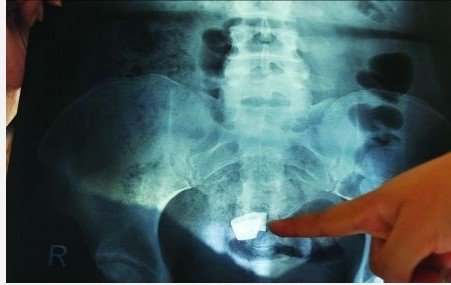

安徽泾县女子破腹产后纱布遗留体内四年 告医院索赔13万

2009年进行破腹产手术后,家住泾县的张女士一直腹痛难忍。今年9月底,她到上海一家医院检查,腹部赫然有块纱布。一怒之下,张女士将妇产医院告上法庭,索赔13万。法院受理后,经过调查,该卫生院认可上述事实。后经调解,卫生院一次性赔偿吕某医疗费、误工费、护理费、残疾赔偿金、精神损害抚慰金等13万元。